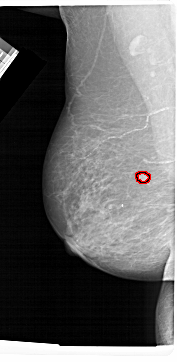

A_1481_1.LEFT_MLO

LEFT_MLO LINES 6871 PIXELS_PER_LINE 3346 BITS_PER_PIXEL 12 RESOLUTION 43.5 OVERLAY

FILE: A_1481_1.LEFT_MLO.OVERLAY

TOTAL_ABNORMALITIES 1

ABNORMALITY 1

LESION_TYPE MASS SHAPE ROUND MARGINS CIRCUMSCRIBED

ASSESSMENT 3

SUBTLETY 4

PATHOLOGY BENIGN

TOTAL_OUTLINES 1

BOUNDARY